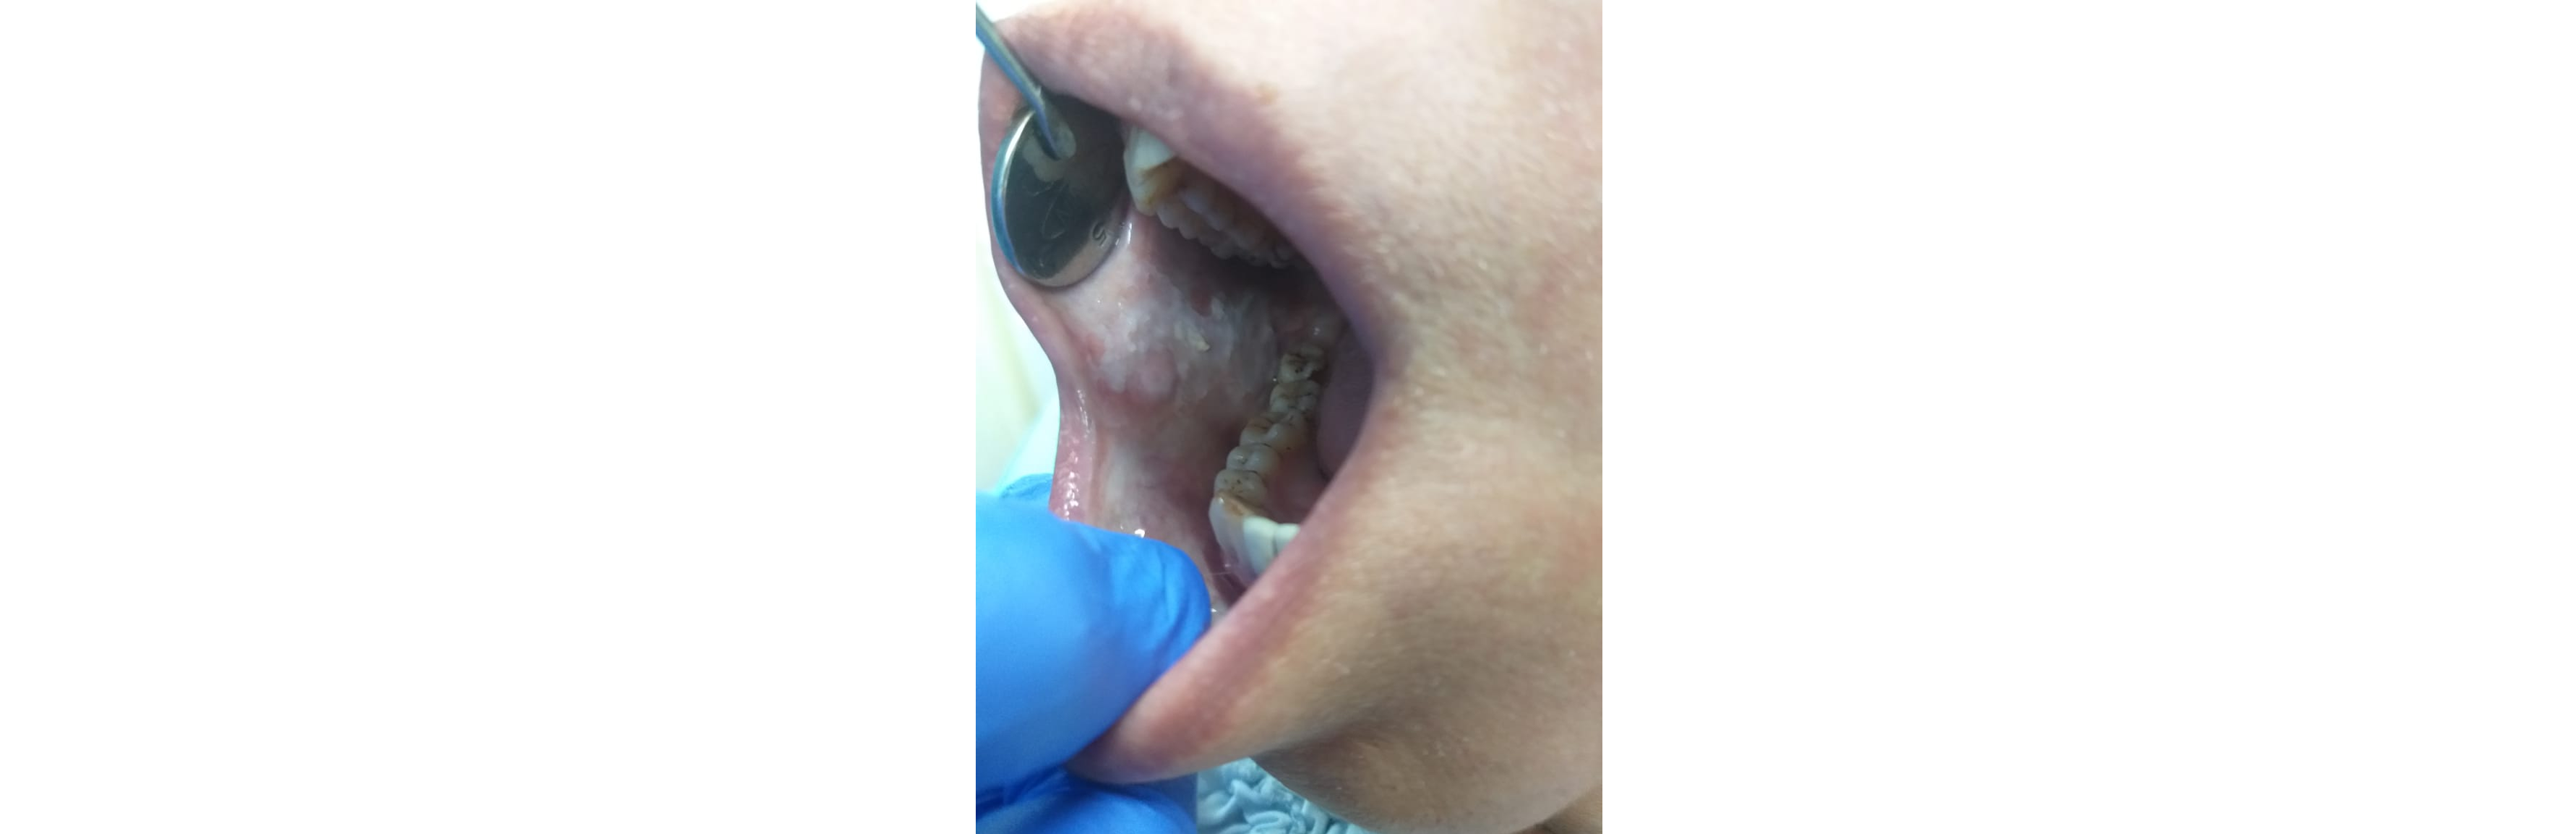

Lesions of the mouth, lip, and tongue encompass a range of conditions that can affect oral health and comfort. Treatment for mouth ulcers and sores involves identifying and addressing the underlying causes, which can include nutritional deficiencies, stress, or systemic diseases. Effective management often includes topical treatments, lifestyle modifications, and in some cases, medications to alleviate pain and promote healing. Ensuring that these lesions are properly evaluated is crucial to rule out more serious conditions and provide appropriate care.

Comprehensive Treatment for Lesions of the Mouth, Lip, and Tongue

Tongue disorders, such as geographic tongue and black hairy tongue, present unique challenges in oral health management. Geographic tongue, characterized by map-like patterns on the tongue’s surface, can cause discomfort and sensitivity. Black hairy tongue, marked by a dark, furry appearance due to the buildup of dead cells and bacteria, often results from poor oral hygiene or certain medications. Both conditions typically respond well to improved oral hygiene practices and, if necessary, specific treatments to manage symptoms and prevent recurrence.